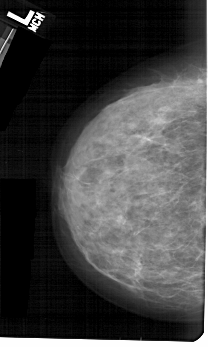

A_1367_1.LEFT_MLO

LEFT_CC LINES 5191 PIXELS_PER_LINE 3106 BITS_PER_PIXEL 12 RESOLUTION 43.5 NON_OVERLAY